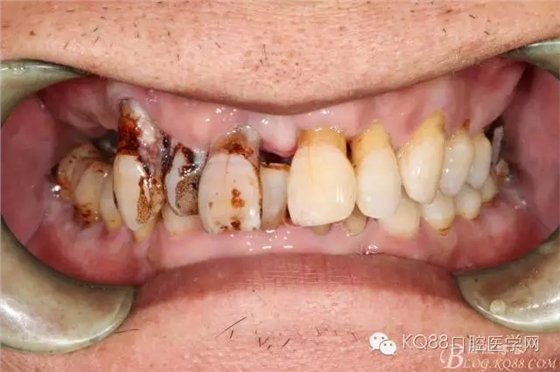

患者 男 57歲

主訴:右上后牙缺失要求修復(fù)

現(xiàn)病史:患者右上前牙松動,右上后牙缺失,要求固定修復(fù)

既往史:吸煙史,拔牙史,其他無異常

檢查:11、12、13Ⅲ度松動,牙齦退縮,根面暴露,14、15、16、17缺失,余牙不同程度牙齦退縮。